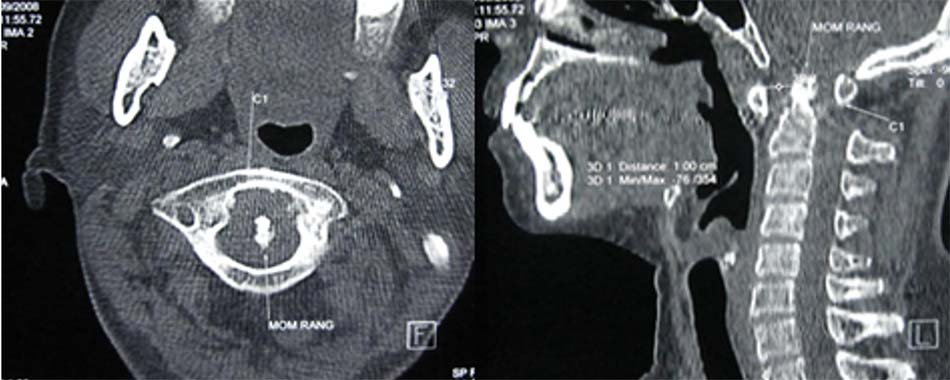

Từ khi có chụp cắt lớp và cộng hưởng từ, người ta có thể phát hiện các thương tổn dây chằng ngang phối hợp với vỡ C1, vì vậy hầu hết đều thống nhất chia làm 2 loại:

- Vỡ C1 đơn thuần: thương tổn vững, điều trị bảo tồn.

- Vỡ C1 kèm rách dây chằng ngang: vỡ cung sau và cung trước C1 có thể làm căng rộng sang bên của hai khối bên gây rách dây chằng ngang. Spence và cộng sự [41] nghiên cứu trên tử thi thấy khi khối bên căng rộng quá 6,9 mm sẽ gây rách hoàn toàn dây chằng ngang. Đây là thương tổn mất vững và dễ di lệch thứ phát [48].

Khi chỉ số Spence > 6,9 chẩn đoán xác định đứt dây chằng ngang, tổn thương mất vững [11] [30] [42].